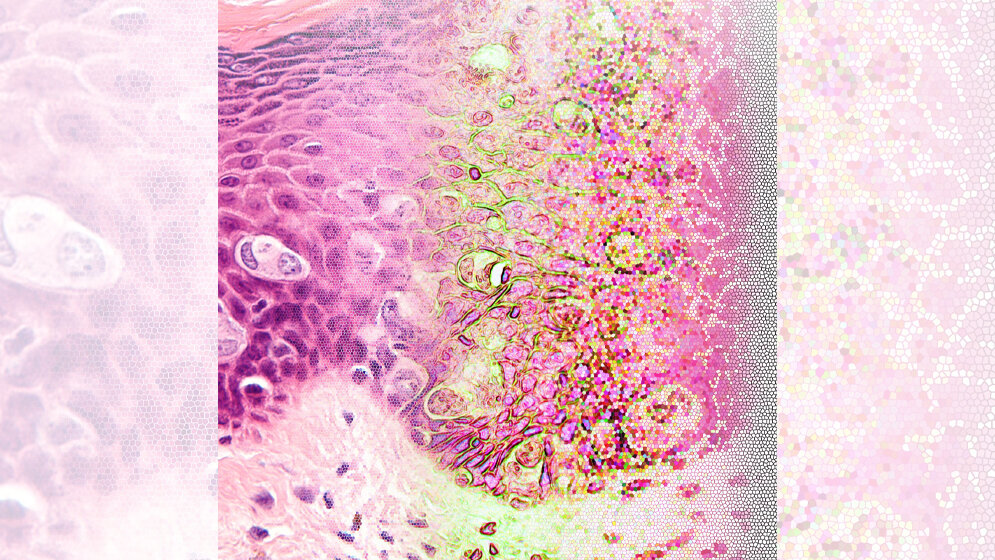

Das Projekt EMPAIA unter Leitung der Charité – Universitätsmedizin Berlin hat sich im Innovationswettbewerb künstliche Intelligenz (KI) des Bundesministeriums für Wirtschaft und Energie (BMWi) durchgesetzt. Jetzt geht es in die Umsetzung. Um Patientinnen und Patienten noch individueller behandeln zu können, wird bei vielen Erkrankungen – insbesondere bei Krebs – eine immer aufwändigere Diagnostik durchgeführt. Vor allem die Auswertung von Bilddaten, wie MRT-Aufnahmen oder Gewebeschnitten, ist zeitintensiv und komplex. Methoden der künstlichen Intelligenz können dabei helfen, die Bilder schneller auf relevante Informationen hin zu analysieren – beispielsweise auf das Vorliegen von Metastasen. „Die künstliche Intelligenz hat großes Potenzial, in den kommenden Jahren alle Bereiche der bildbasierten medizinischen Diagnostik zu revolutionieren“, sagt Prof. Dr. Peter Hufnagl vom Institut für Pathologie der Charité. Der Koordinator des EMPAIA-Konsortiums („Ecosystem for Pathology Diagnostics with AI Assistance“) erklärt: „Dieses Potenzial lässt sich derzeit jedoch kaum nutzen, weil die Infrastruktur fehlt, es keine Standards gibt und die rechtlichen Rahmenbedingungen nicht geklärt sind.“

Zusammen mit dem DAI-Labor der Technischen Universität Berlin, dem Fraunhofer-Institut für Digitale Medizin MEVIS, der Vitasystems GmbH und der Qualitätssicherungs-Initiative Pathologie QuIP GmbH möchte Prof. Hufnagl deshalb eine Plattform aufbauen, die Ärztinnen und Ärzten einen leichten Zugang zu zertifizierten und validierten KI-basierten Apps ermöglicht. Die Nutzer sollen beispielsweise vergleichen können, wie verschiedene Programme ein bestimmtes Problem lösen. Gleichzeitig sollen Entwickler von KI-basierten Algorithmen für die Validierung ihrer Software auf Bilddaten zugreifen können. Um die Zertifizierung von Algorithmen für den Einsatz in der Diagnostik zu beschleunigen, wird die Plattform außerdem Entwickler, Referenzinstitute und Zertifizierer zusammenbringen. „Die Spielregeln auf diesem Marktplatz werden sich natürlich nach den geltenden Gesetzen zu Datenschutz und der Zulassung von Medizinprodukten richten“, betont Prof. Hufnagl. „Durch Schaffung dieses Marktplatzes unter klaren rechtlichen Bedingungen möchten wir dazu beitragen, dass Medizinerinnen und Mediziner zugelassene KI-unterstützte Programme in Zukunft routinemäßig für die bildbasierte Diagnostik einsetzen können.“ Das Konsortium plant, die Plattform zunächst auf die Analyse von Gewebeschnitten auszurichten, bevor radiologische Bilddaten in den Fokus genommen werden.